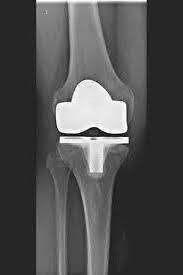

L’articulation artificielle du genou remplace la surface cartilagineuse détruite par l’arthrose. L'os sous-jacent du fémur et de la tête tibiale reste intact. Certains comparent une articulation artificielle moderne du genou à un couronnement de dent ; le terme exact est ce qu'on appelle le resurfaçage bicondylien. Entre les nouvelles surfaces sur la partie supérieure et inférieure de la jambe se trouve ce que l'on appelle une incrustation en plastique blanc spécialement durci, qui peut être vue sur l'image radiographique comme la distance entre les pièces métalliques.